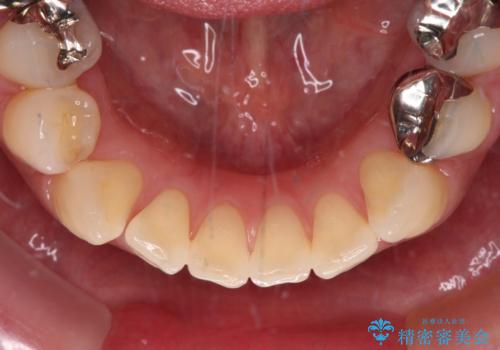

中途半端な矯正治療と前歯の欠損 再矯正とオールセラミッククラウンによる補綴治療

- 矯正治療を行ったものの、隙間やデコボコが多く、欠損している前歯も気になるとのことで来院された患者様です。

当初はセラミック治療だけを希望されていましたが、上下前歯のデコボコが顕著であったため、セラミッククラウンにて治療する前に再度矯正治療を行った方が仕上がりがきれいになると説明し、再矯正を行うこととしました。

矯正治療により前歯横幅のバランスを整えた後に、上顎前歯をオールセラミックブリッジにて補綴治療を行うこととしました。

舌突出癖により、上下前歯が突出して離開してしまったため、舌のトレーニングを徹底的に行いました。